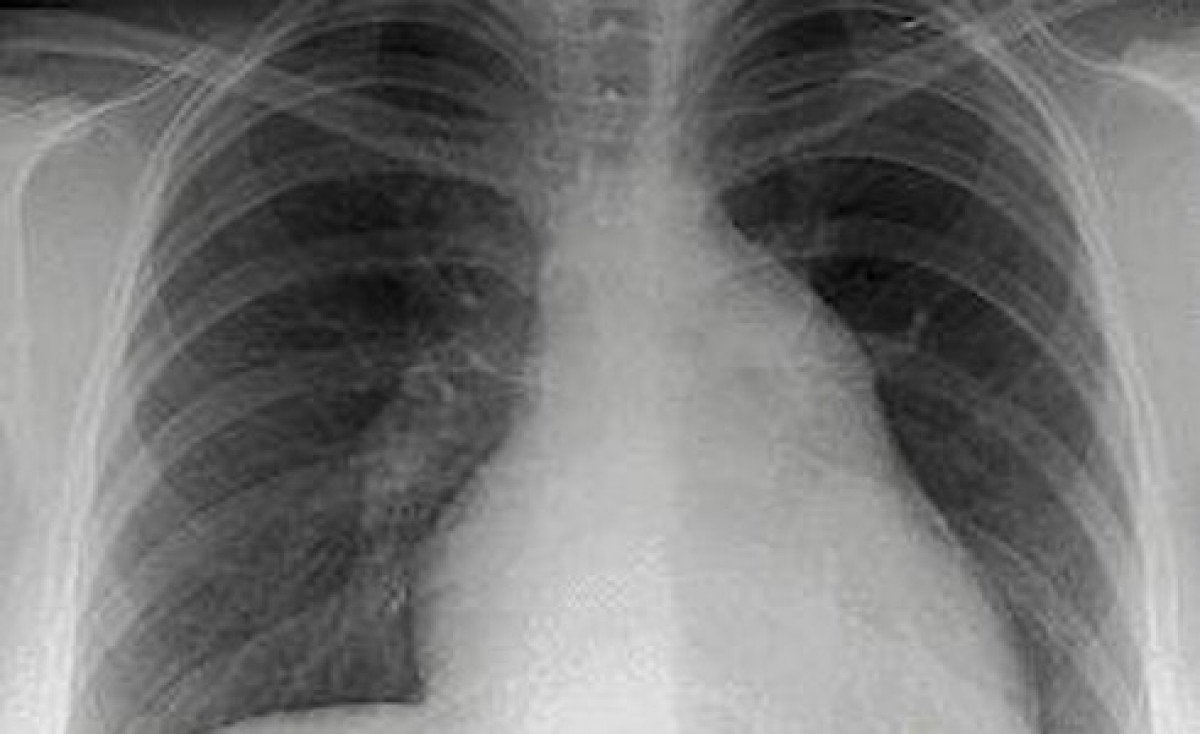

Pulmon con cáncer